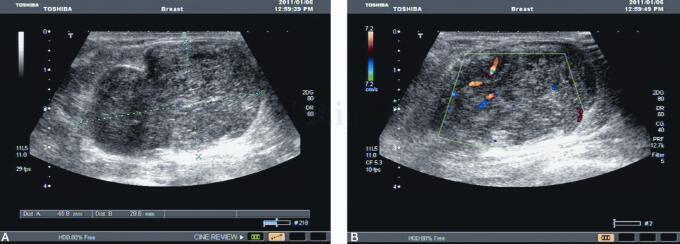

图2 左乳腺超声

左乳腺体回声粗糙,可见4.6cm×4.6cm×3.0cm实性肿物,边界清,内呈低回声,CDFI可检出丰富血流信号,腋下未见明显肿大淋巴结